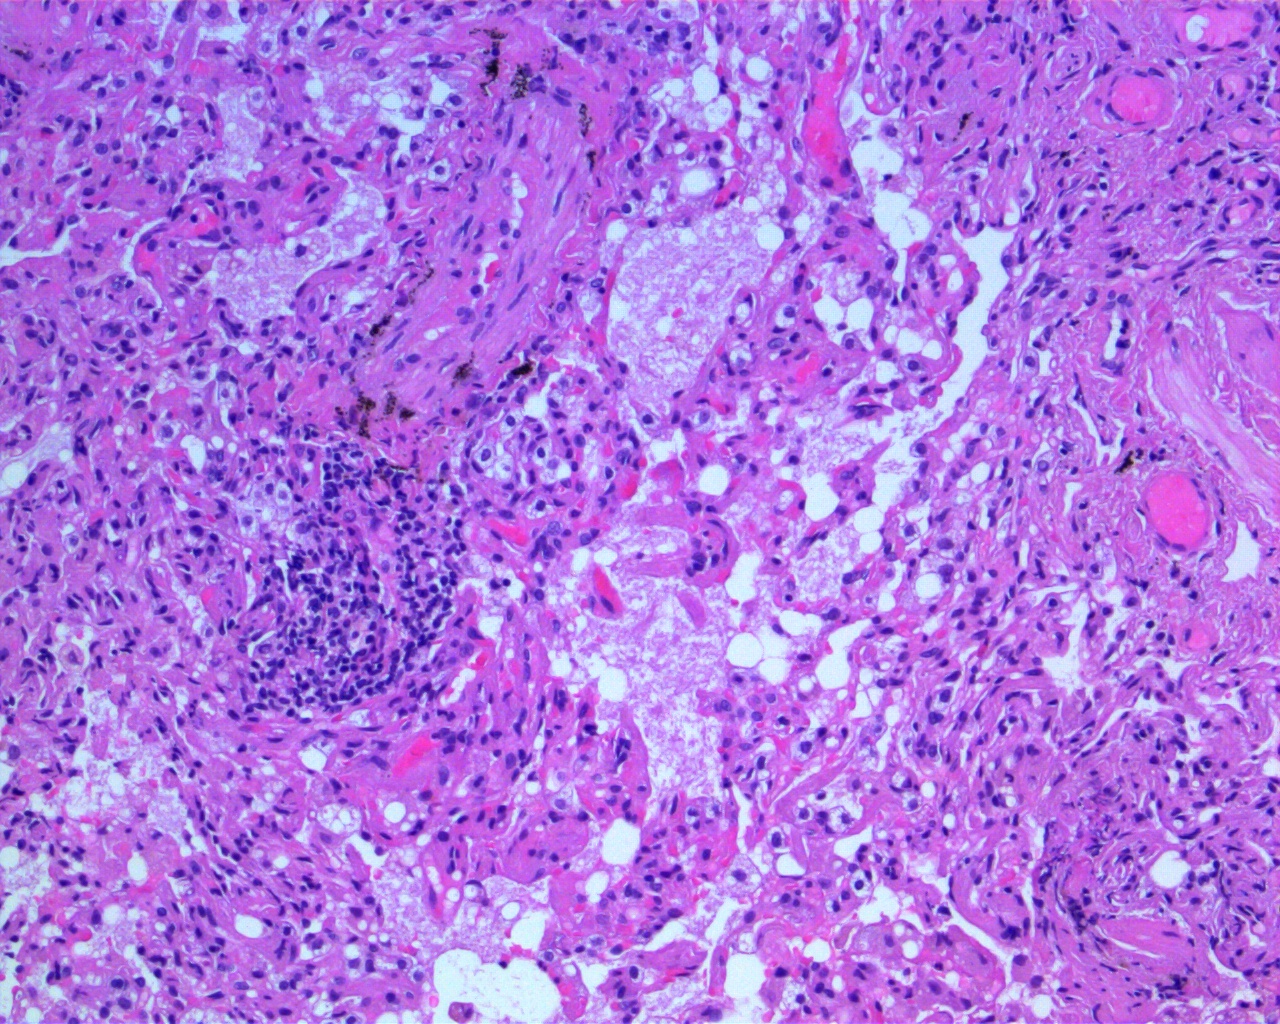

H&E Breast Slide H&E Breast Slide H&E Breast Slide

The nuclear pleomorphism and mitotic activity suggest Grade 2 invasive ductal carcinoma. Stromal invasion pattern is clear.

Findings align with Grade 2 invasive ductal carcinoma. Stromal invasion is evident; ER/PR/HER2 testing is recommended.

H&E Breast Slide

Breast H&E